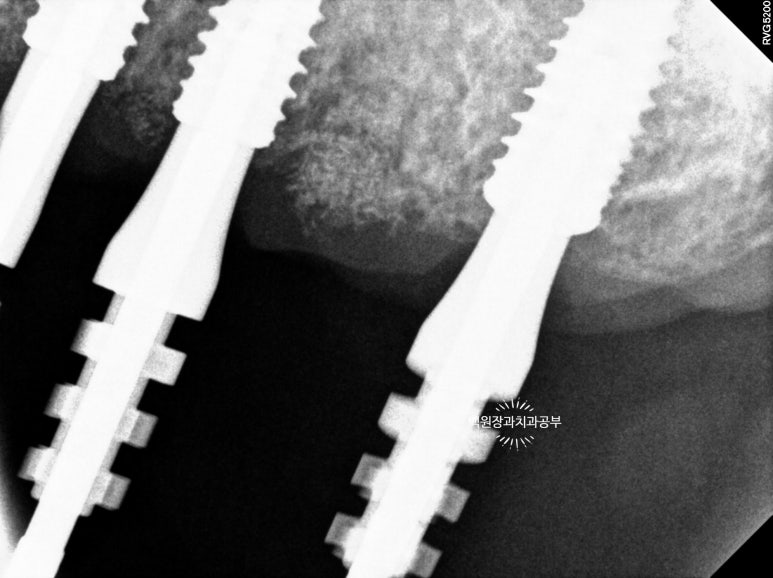

위 아래 임플란트 1차 수술 후 체크업 : coverscrew 노출도 보이긴 합니다.

위턱뼈의 경우 임플란트 1차수술 후 2달, 아래턱뼈의 경우 임플란트 1차수술 후 1달 뒤 임상 사진입니다.

보시면 임플란트가 보이는 곳도 있고 보이지 않는 곳도 있는데요, 바로 '치유 지대주 (=healing abutment)'를 임플란트 1차 수술 때 연결하고와 안하고의 차이입니다. (수은 전지처럼 보이는 은색 뚜껑이 치유 지대주 입니다.)

제가 계속 임플란트 1차 수술이라는 표현을 쓰고 있는데, 그럼 임플란트 2차 수술도 있겠죠? 바로 이 '치유 지대주'를 연결하여 주는 것이 임플란트 2차 수술입니다.

그럼 왜 '치유 지대주'를 어떤 것은 연결하고 어떤 것은 연결하지 못했을까요?

임플란트 주변에 '뼈이식'을 해야하는 경우 '치유 지대주'를 연결하기가 힘듭니다.치유지대주의 주변의 잇몸 사이로 뼈이식 재료가 다 빠져나오기 때문이에요. 그래서 뼈이식을 동반하는 경우 주로 임플란트 1차수술까지만 하게 되는 것이죠. 그러면 수술을 마치고 나서 잇몸만 보일 뿐인 상태가 됩니다.